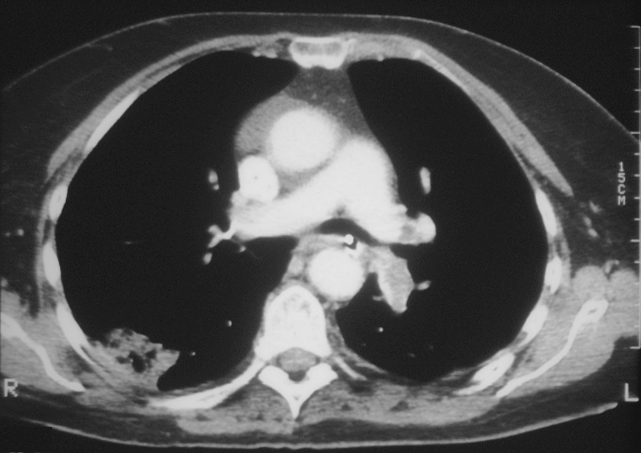

EMBOLIA PULMONAR

Cóagulos observados por Tomografía Computarizada